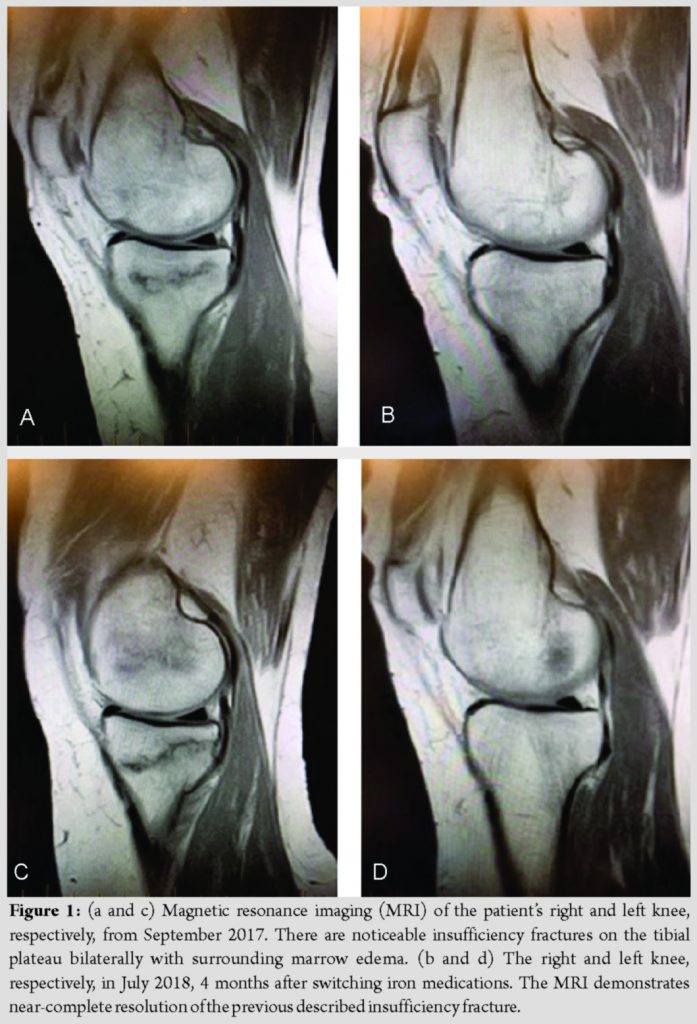

In December 2016, a 61-year-old woman was referred to our orthopedic clinic suffering from bilateral upper thigh pain. Amagnetic resonance imaging (MRI) revealed a displaced fracture on the right femoral neck and a non-displaced fracture on the left femoral neck. Her medical history was characterized by hepatitis C with cirrhosis, varices, and hypersplenism, leading to thrombocytopenia. She reports she received FCM injections every 4 weeks for her anemia. In February 2017, the patient underwent total hip arthroplasty on her right side and a pinning of her left hip. In May 2017, the patient returned to the clinic due to bilateral knee pain. MRI revealed insufficiency fractures of the right medial distal femur and right medial tibial plateau (Fig. 1a). The left knee demonstrated an insufficiency fracture of the medial tibial plateau with extensive surrounding marrow edema (Fig. 1c). Laboratory data from July 2017 indicated hypophosphatemia and increased alkaline phosphatase (Table 1). Serum calcium, parathyroid hormone, thyroid-stimulating hormone, and Vitamin D, 25-hydroxy were all normal (Table 1). Bone mineral density assessment by dual-energy X-ray absorptiometry qualified her bone loss as osteoporosis. In March 2018, the patient’s hematologist switched her iron medication to iron sucrose (IS). After switching medications, her serum phosphate and FGF23 levels normalized (Tables 1 and 2) and MRI revealed near-complete healing of her insufficiency fractures bilaterally (Fig. 1b and d).